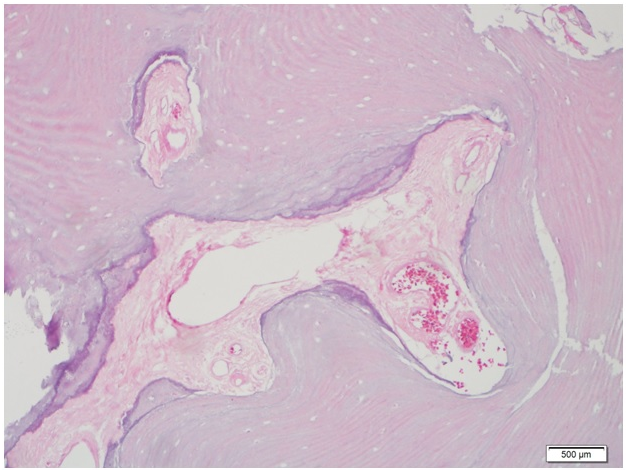

The resection of tumor was performed using posterior transmastoid approach (Figure 2). After a cortical mastoidectomy, the mastoid segment of the facial nerve was identified and followed down till the SMF. The osteoma was identified in the anteroinferior part of the mastoid process about 1mm lateral to the fallopian canal; the posterior and inferior walls of the EAC were replaced by the tumor which was filling the lateral part of the EAC and extending inferiorly on the vaginal process till the base of styloid process. A gradual drilling around the tumor was performed, taking care of the proximity of the facial nerve, till the mass was complete excised en bloc. Reconstruction of the EAC was done using tragal cartilage and fascia that was covered by the remaining skin. The canal was dressed with gauze with antibiotic and corticoid unguent for 2weeks (Figure 2). The postoperative period was smooth, facial nerve function was intact. Three weeks later, the EAC dressing was removed; the canal was patent and wide and completely epithelized. Histopathology result confirmed the diagnosis of osteoma (Figure 3).

Figure 3 Microscopic description:"Sections show dense, mature, predominantly lamellar bone. Interosseous space is mostly composed of scant fibrovascular tissue.